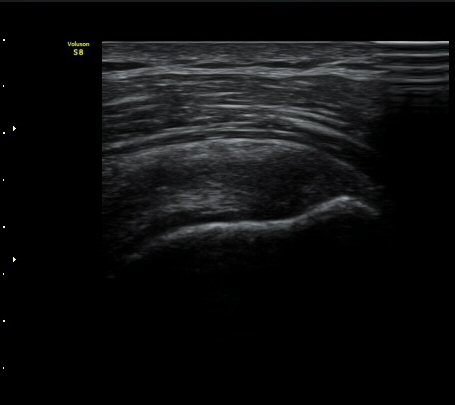

±Ø»ó°Ç Á¾´Ü¸é°Ë»ç½Ã ±Ø»ó°Ç ºÎÂøºÎ¿¡ Àú¿¡ÄÚ ºÎÁ¾°ú ¹Ì¼¼ÇÑ °Ç ¿¬°á¼º ¼Ò½ÇÀÌ

°üÂûµÊ (±×¸² 1, 2, 3 )

±Ø»ó°Ç Ⱦ´Ü¸é°Ë»ç½Ã ±Ø»ó°Ç ÀϺΠÀú¿¡ÄÚ ºÎÁ¾°ú ¹Ì¼¼ÇÑ °Ç ¿¬°á¼º ¼Ò½ÇÀÌ °üÂûµÊ(±×¸² 4, 5).

±×¸² 4)¿¡¼­ °üÀý¿¬°ñ°æ°è¸é ¡ÈÄ(articular interface sign)°¡ °üÂûµÊ.